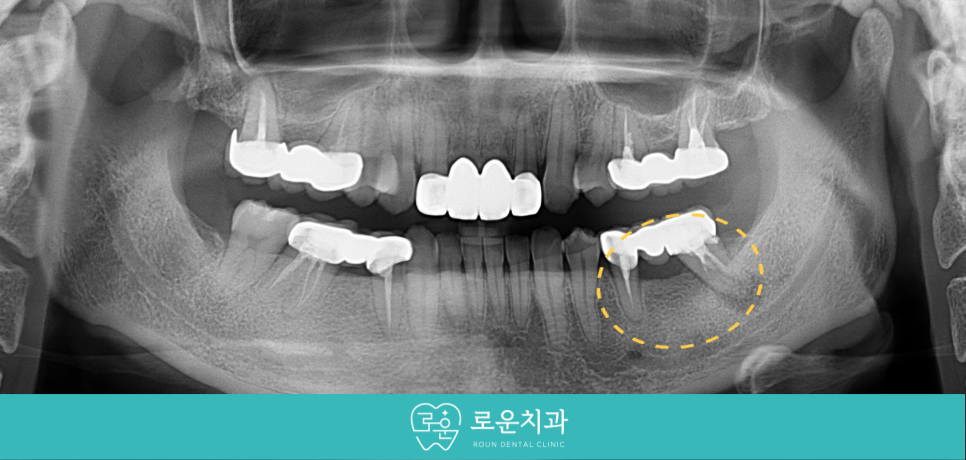

오늘 소개해 드릴 환자분께서는 30대 여성분으로

아래턱 왼쪽 아래 과거 보철물을 수복했던 부위에서

통증과 흔들림이 느껴지신다며

검사와 치료를 위해 찾아주셨습니다.

먼저 구강 내에서

확인해 보았더니

아래턱 왼쪽 어금니 부위

기존 브릿지 보철물의 맨 뒤의 치아에서

심한 동요도가 있었는데요.

정밀한 검사를 위해

파노라마 사진을 촬영해 보았더니

두 지대치 모두 뿌리 끝 염증이 있었지만

특히 맨 뒤의 두 번째 큰 어금니(#37)가

더 심하였으며 동요도까지 있었는데요.